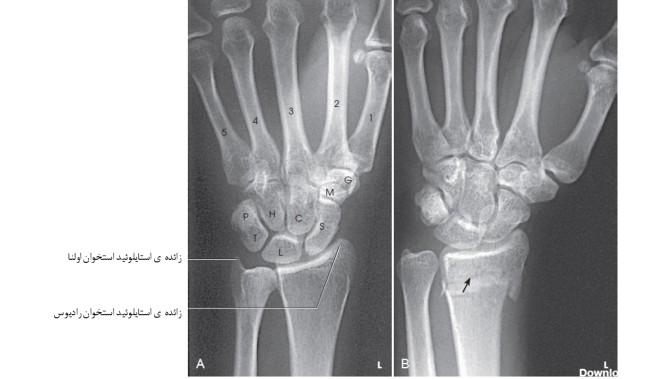

عکس رادیوگرافی مچ دست

همه چیز در مورد رادیولوژی دست. این روش چگونه انجام می شود؟ حطرات این روش کدامند؟ نوبت گیری برای رادیولوژی دست و ...